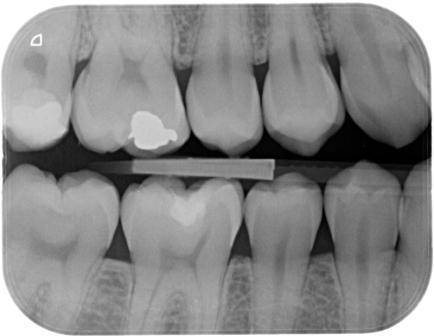

Nel nostro Studio impieghiamo un sistema radiografico computerizzato, il Vista Scan Plus della Dürr che consente di ottenere immagini di alta qualità (vedi confronto analogico/digitale) con dosi radiogene sensibilmente più basse per il paziente.

Con Vistascan Plus siamo in grado di ottenere, nel giro di pochi minuti, tutte le immagini che ci servono per un corretto ausilio diagnostico: bitewing, endorali, ortopantomografie, teleradiografie.